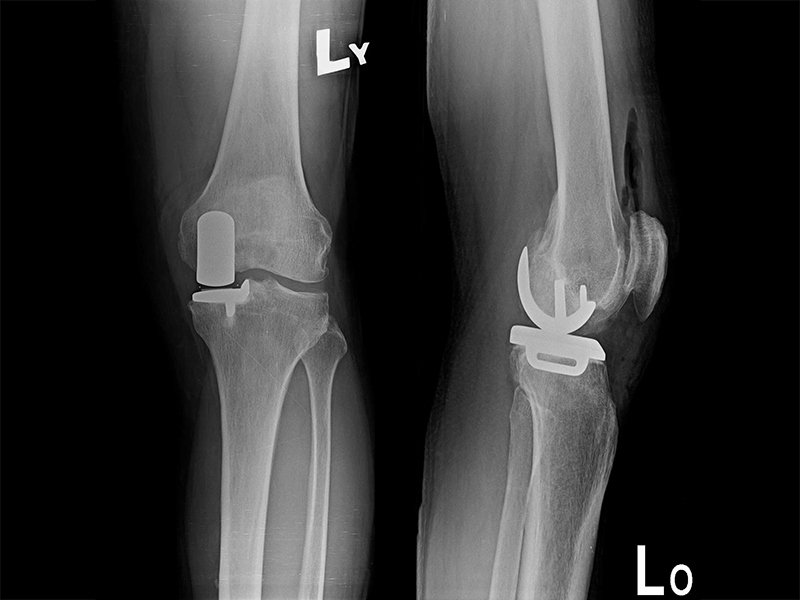

傳統部分膝置換

更多